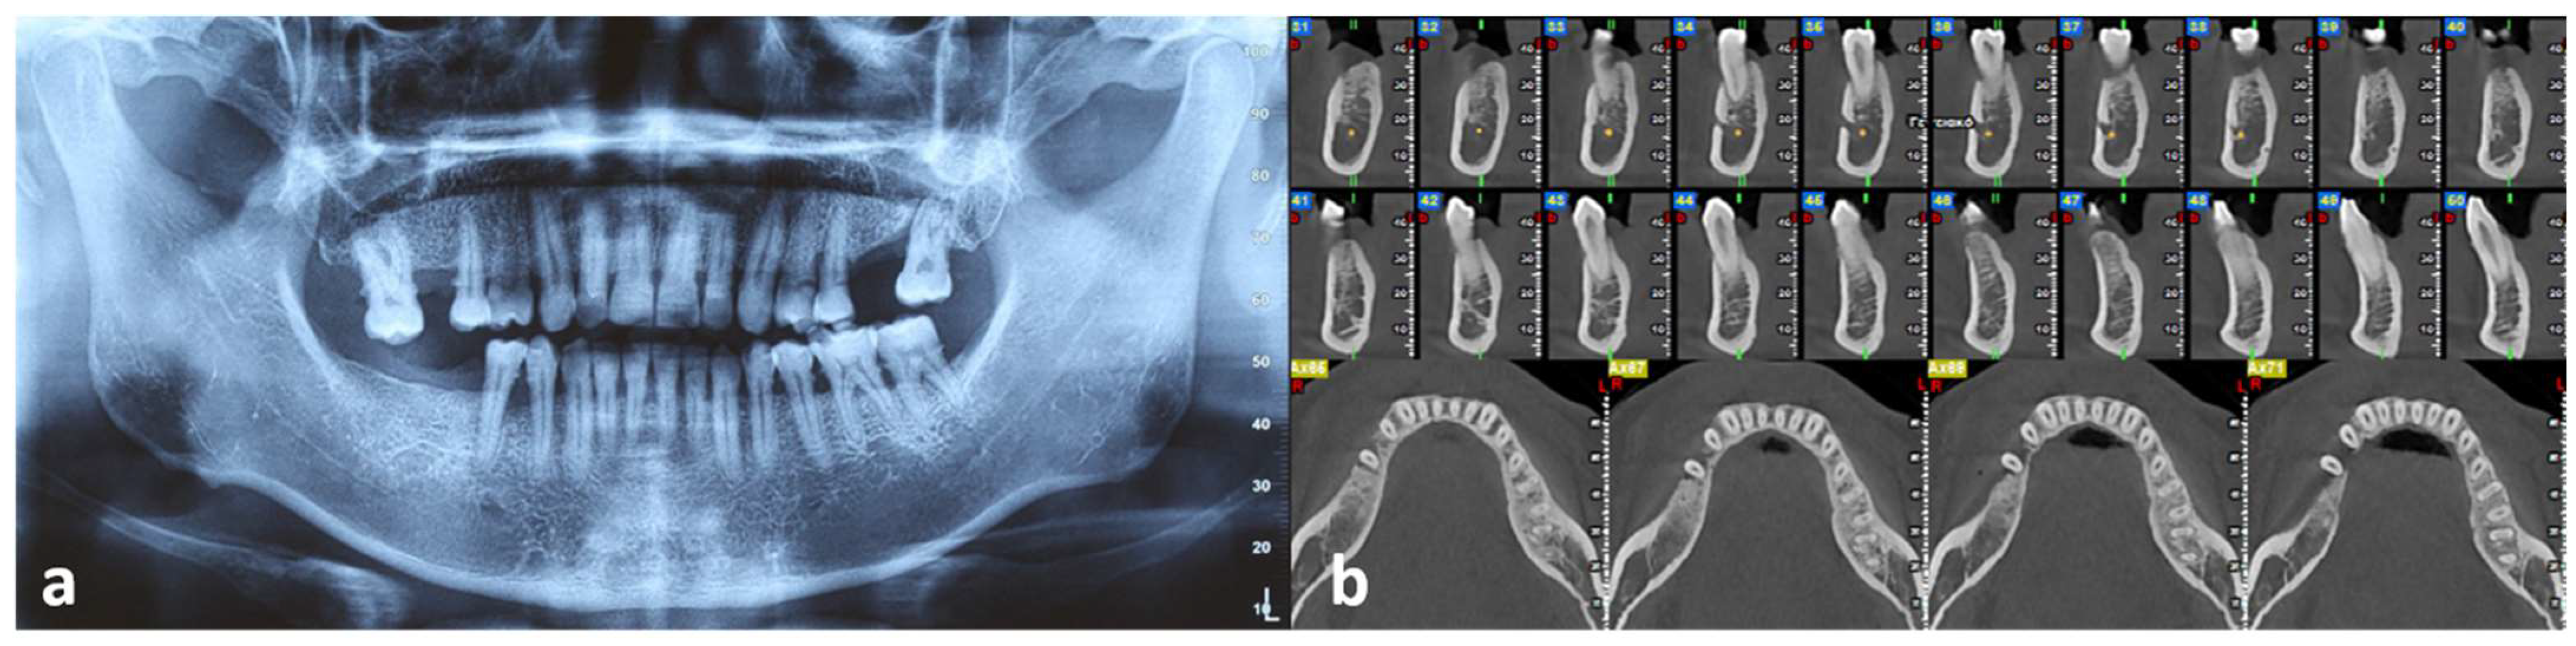

2. Case Report